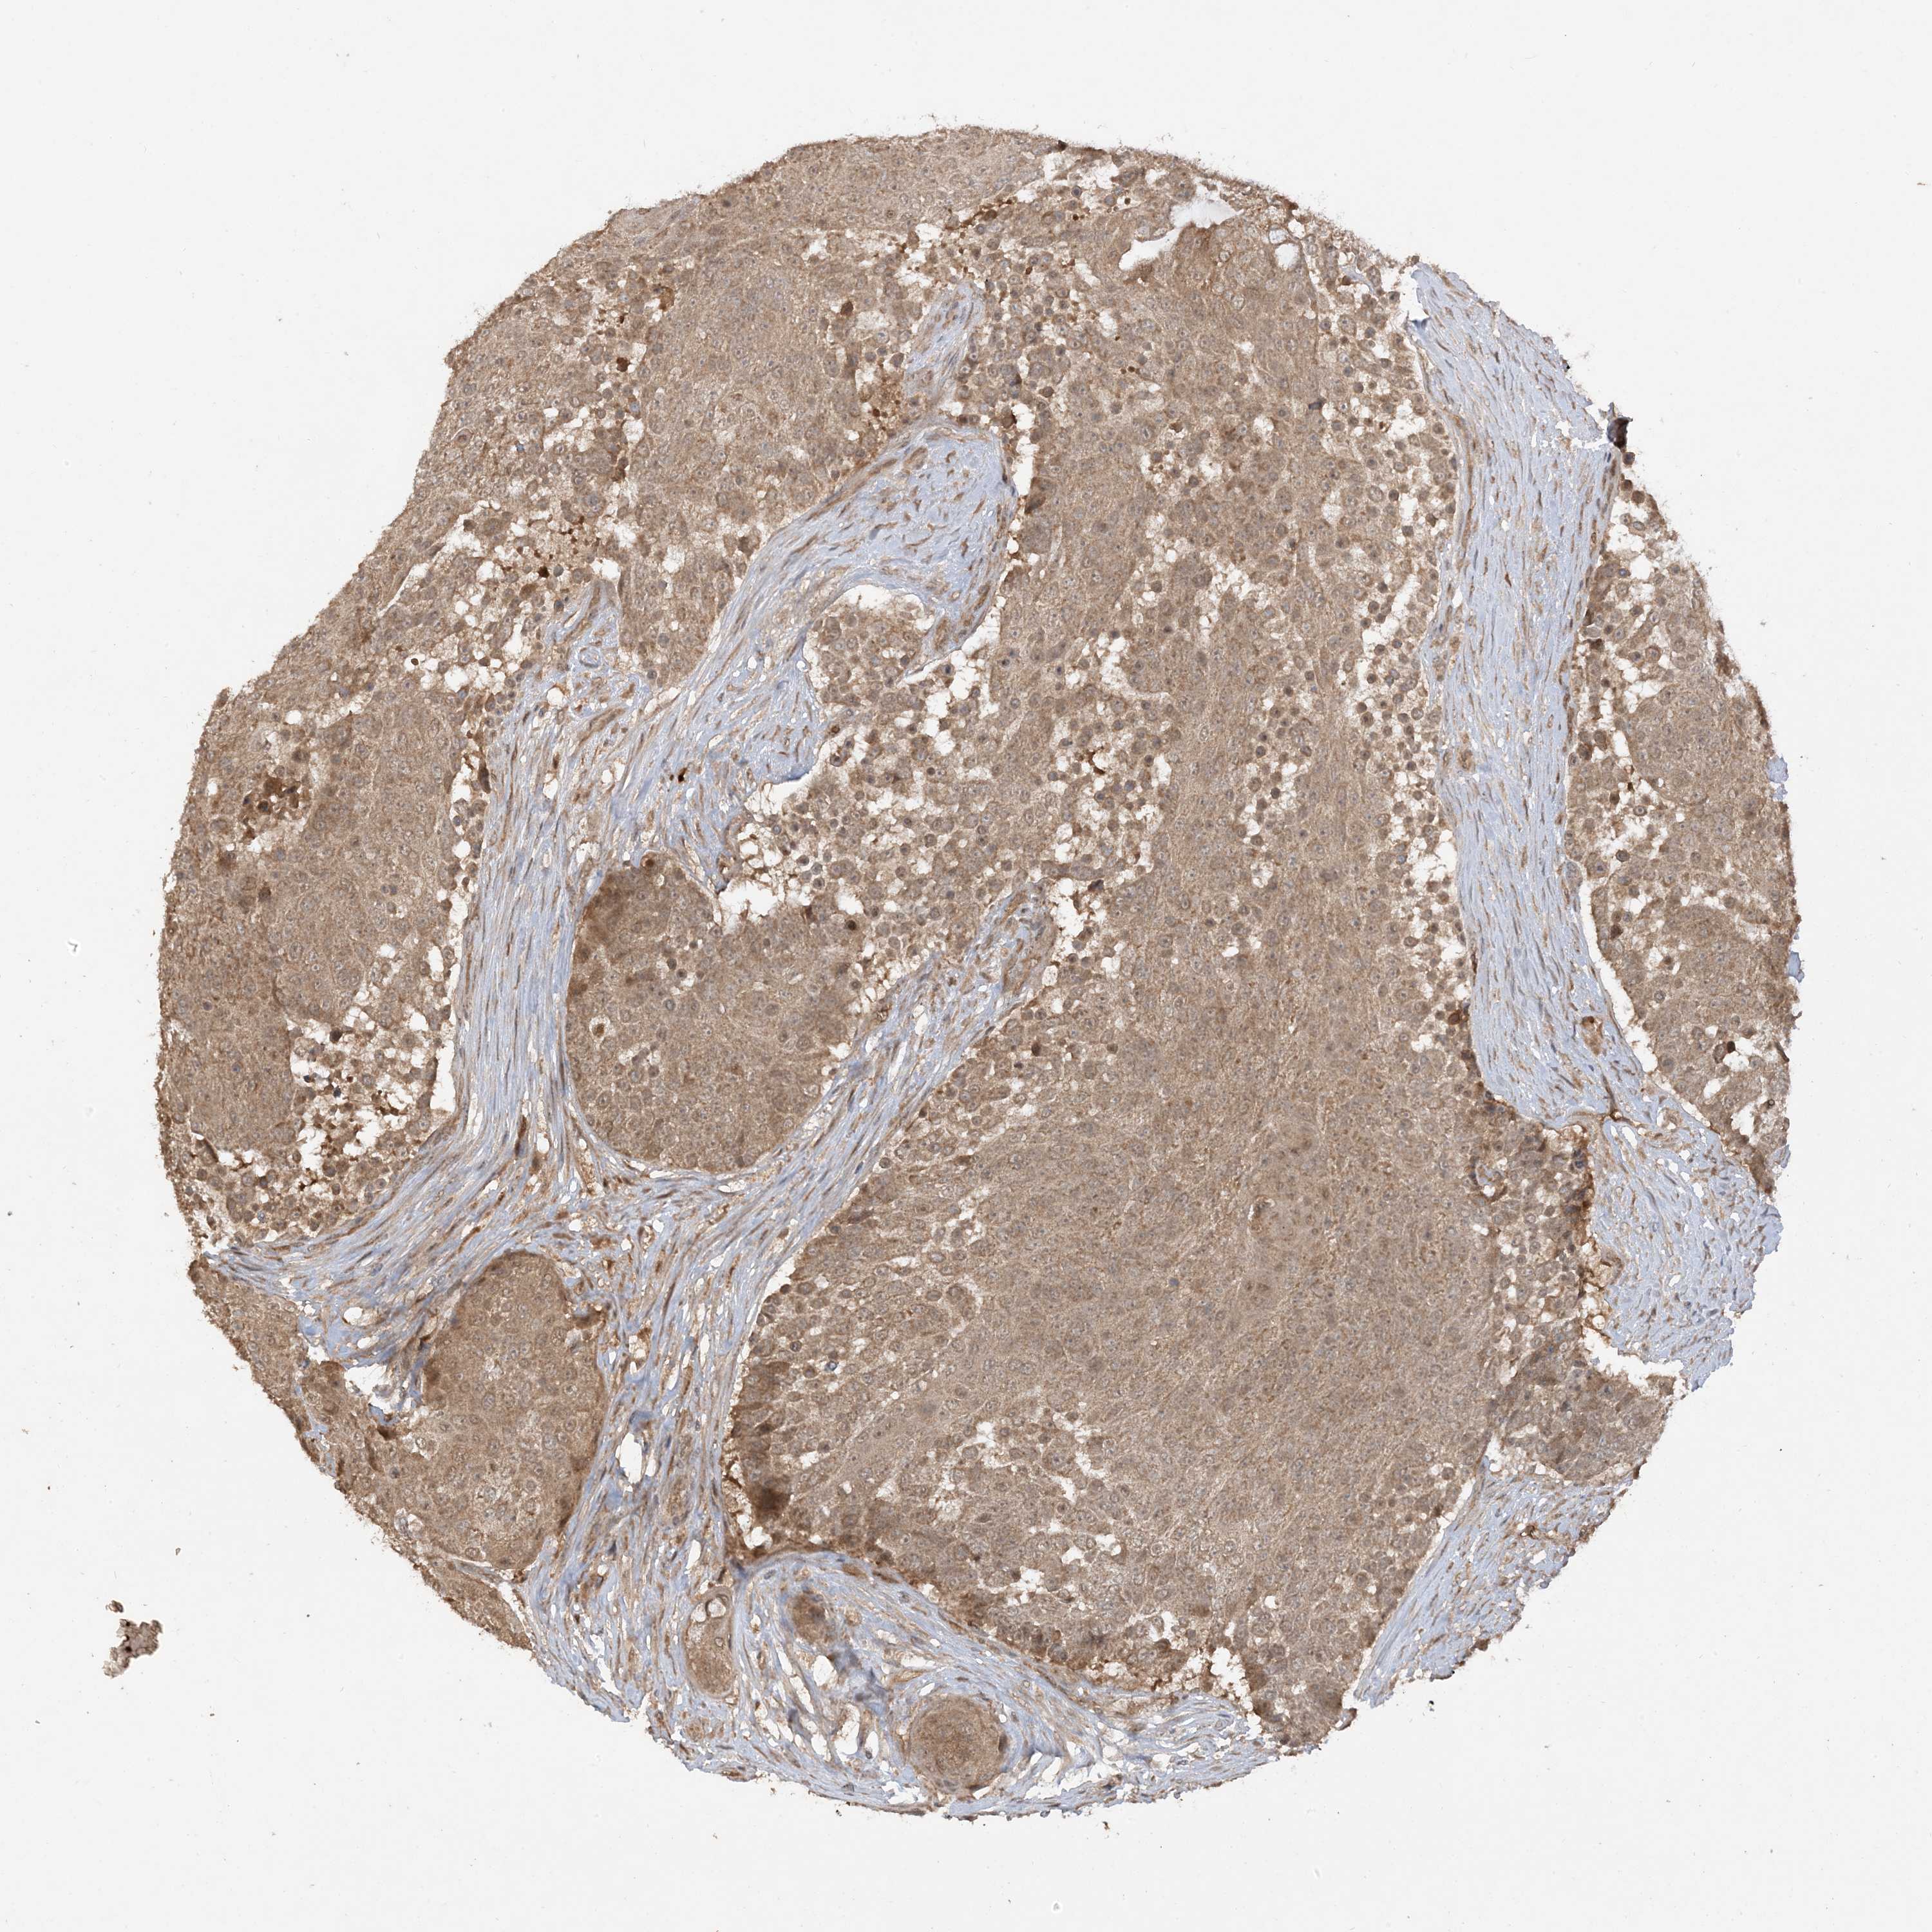

UROTHELIAL CANCER - Protein expressioni

A mouse-over function shows sample information and annotation data. Click on an image to view it in a full screen mode. Samples can be filtered based on level of antibody staining by selecting one or several of the following categories: high, medium, low and not detected. The assay and annotation is described here.

Note that samples used for immunohistochemistry by the Human Protein Atlas do not correspond to samples in the TCGA dataset.

Antibody stainingi

Antibody staining in the annotated cell types in the current human tissue is reported as not detected, low, medium, or high, based on conventional immunohistochemistry profiling in selected tissues. This score is based on the combination of the staining intensity and fraction of stained cells.

Each image is clickable and will lead to virtual microscopy that enables deeper exploration of all samples and also displays staining intensity scores, fraction scores and subcellular localization as well as patient and tissue information for each sample.

Antibody HPA032057

Staining

High

Medium

Low

Not detected

Intensity

Strong

Moderate

Weak

Negative

Quantity

>75%

75%-25%

<25%

None

Location

Nuclear

Cytoplasmic/membranous

Cytoplasmic/membranous,nuclear

Urothelial carcinoma, Low grade

Urothelial carcinoma, High grade